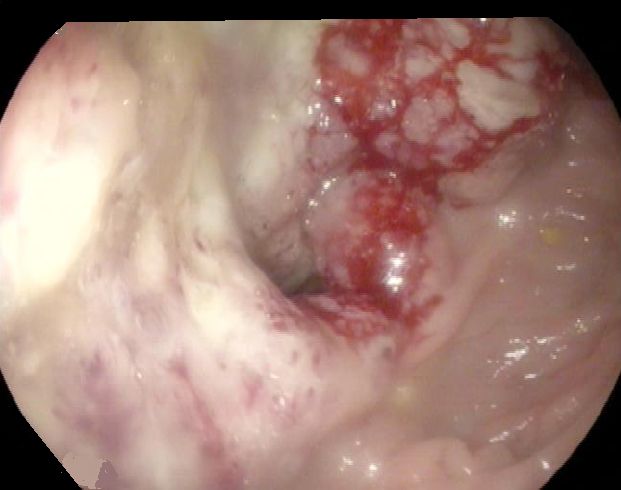

Anastomosen - Rezidiv 66-jähriger Mann, der vor 6 Monaten ein Karzinom der rechten Colonflexur hatte. Postoperativ pT3d pN2a (6/23)cM1a(PUL) L1 V0 Pn0. Adjuvant Bevacizumab/FOLFIRI. Jetzt endoskopisch Tumornachweis an der Anastomose.